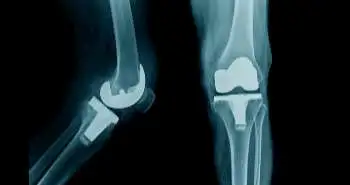

Is there any association between statin use and postoperative pain outcomes in patients who undergoes total knee arthroplasty?

Perioperative statin use in patients undergoing total knee arthroplasty is associated with reduced consumption of opioids.

Consumption of perioperative statin accompanies with enhanced postoperative opioid consumption following total knee arthroplasty executed under spinal anaesthesia, as evident from the findings of a recently published retrospective, observational study in the Journal of Regional Anesthesia & Pain Medicine.

Medical records of patients who underwent elective total knee arthroplasty under spinal anaesthesia were analyzed as inpatients in a tertiary hospital from January 2005 to October 2017. The postoperative day (POD) 3 of patients who took preoperative statins and of patients who did not receive preoperative statins were compared to assess the pain outcomes.

One thousand eighty-eight propensity-matched participants were selected for the final analysis. The patients who took statins showed a higher rate of total morphine equivalent consumption through POD 3 as compared to the non-statin group, but with comparable NRS pain scores. Although the rise in morphine consumption was minimal, therefore, its clinical significance remains debatable.